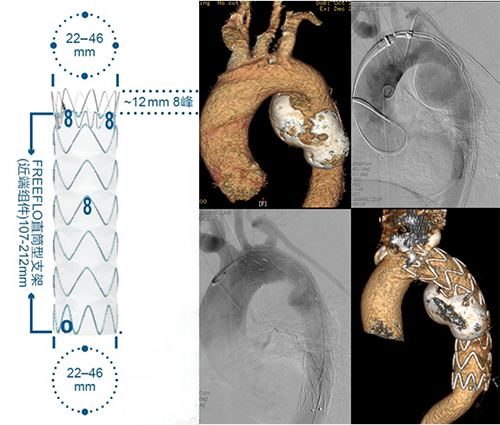

胸、腹主动脉瘤是血管外科常见疾病,瘤体一旦破裂出血,死亡率大于90%。传统治疗方式通常采用开胸开腹的外科手术,切除病变动脉瘤并用人工血管代替该段病变血管,围手术期并发症发生率及死亡率高。尽管手术创口巨大,一旦顺利度过围手术期,远期结果满意。与传统的外科手术相比较,血管外科更加微创的主动脉瘤腔内修复术是在DSA透视下,经双侧股动脉直接穿刺预留缝合线结,将折叠的覆膜金属自膨支架送入胸腹主动脉内,将覆膜支架固定于动脉瘤近端的正常动脉壁,远端通过支架拼接建立分叉型的远端血流通路,保障盆腔和下肢血供。胸/腹主动脉瘤的腔内修复术(EVAR)具有创伤小、恢复快的优点,已经逐渐成为首选的、主流的微创治疗方法,尤其适合高危高龄、手术耐受力差而无法耐受传统经胸经腹开放手术的患者。

胸主动脉瘤腔内修复术治疗胸降主动脉瘤(TEVAR)

支架经个体化改制后的开窗-分支支架